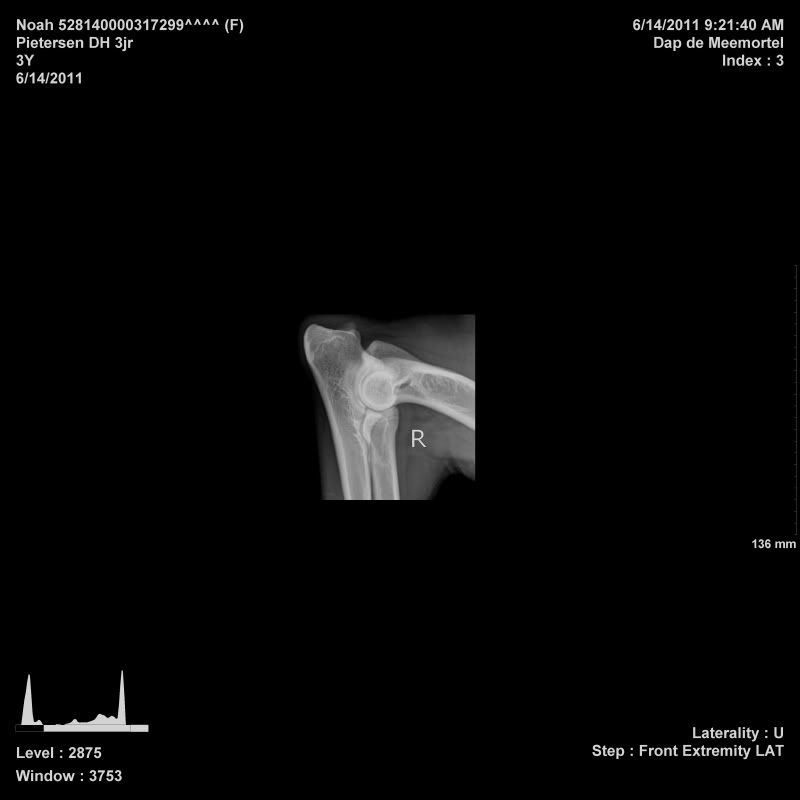

Noah is toen ze 11 maanden gerontged op ellebogen en heupen, dat was toen helemaal goed. Daarna 2 jaar fanatiek gaan sporten (1x in de week flyball, 2x in de week ipo). Voor mijzelf wilde ik graag weten wat 2 jaar sporten voor invloed heeft op de gewrichten, zodoende ben ik vandaag wezen rontgen in Budel. Ze is ook meteen gecastreerd, zodat ze maar 1x onder narcose moest

Haar heupen, ellebogen en rug waren wederom perfect! De DA was te spreken over haar gewrichten

Afbeelding